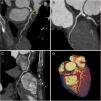

Due to intermediate risk findings on the treadmill test, coronary computed tomography angiography (CCTA) was requested for further assessment. The coronary calcium score was 105.2 Agatston units and an intermediate stenosis was identified in the proximal left anterior descending artery (LAD) due to non-calcified plaque (Figure 1A and D, arrow). Because the physiologic significance of the lesion was unclear, computed tomography-derived fractional flow reserve (CT-FFR) was determined using a workstation-based software prototype (cFFR, Siemens AG Healthcare, Forchheim, Germany). The value of CT-FFR just beyond the proximal LAD stenosis was 0.75 (Figure 2). The patient was referred for invasive coronary angiography (ICA) which confirmed a 75% stenosis in the proximal LAD (Figure 3B and Supplementary Video S1). Invasive FFR assessed in the LAD showed a similar result (0.76) to that observed on CCTA (Figures 3A and 3C). The patient successfully underwent percutaneous coronary intervention with a drug-eluting stent (Figure 4) and was asymptomatic after the procedure. This case illustrates the value of CT-FFR as a gatekeeper prior to ICA, to appropriately select patients and vessels for revascularization.

Coronary computed tomography angiography images. Curved multiplanar reformats of the left anterior descending artery (LAD) (A), left circumflex artery (B) and right coronary artery (C); three-dimensional volume rendering image of the heart (D). Note the presence of significant stenosis in the proximal LAD due to non-calcified plaque (arrows).